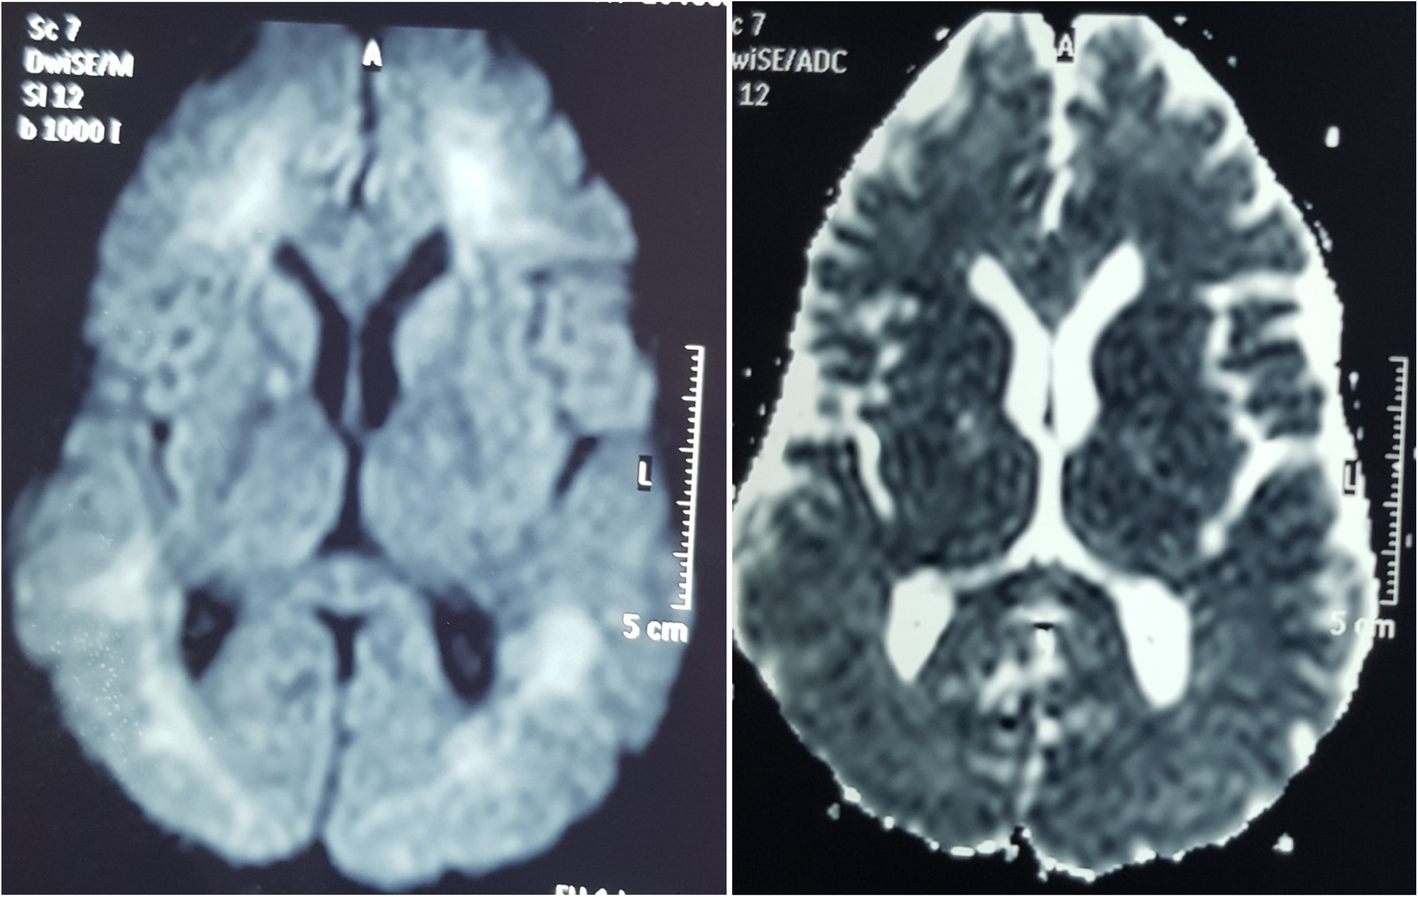

Fig. 4From: A case of delayed neurological manifestation following carbon monoxide poisoning in Sri Lanka: epidemiology of exposure and literature reviewMRI brain showing high signals in DWI images with no significant changes appreciated on ADC map in subcortical white matter, globus pallidusBack to article page